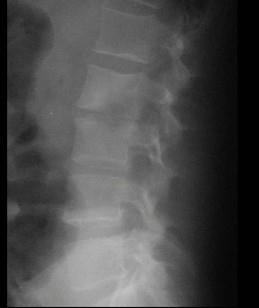

问题 男,53岁,高热,寒战,背痛半月余,请结合影像学检查选出最可能的诊断 ( )

选项 A、强直性脊柱炎 B、椎体压缩骨折 C、脊柱骨髓炎 D、脊柱结核 E、脊柱转移瘤

答案 C